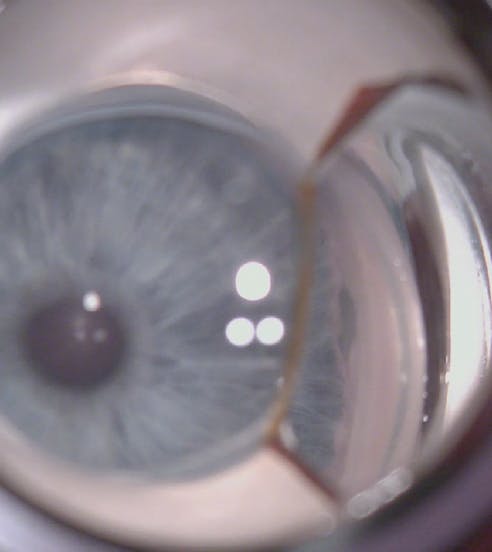

On examination, UCVA was 20/150 with a pinhole acuity of 20/40 OD and 20/25 OS. IOP was 3 mm Hg OD and 13 mm Hg OS. Notable findings at the slit lamp were corneal folds in the right eye and a well-positioned posterior chamber IOL in each eye. A fundus examination revealed moderate cupping of both optic nerves and macular folds in the right eye. Gonioscopy showed a grade IV angle with a nasal cyclodialysis of 1.5 clock hours in the nasal angle of the right eye (Figure 1) and a well-positioned first-generation iStent Trabecular Micro-Bypass Stent (Glaukos) in the nasal angle of the left eye. OCT imaging revealed optic nerve cupping and macular folds (Figures 2 and 3).

After the eye was pressurized with an OVD, the cleft was visualized and marked. A peritomy and a scleral flap were created. An incision was then made though the sclera with care taken to stop short of penetrating the choroid. Several interrupted 10-0 nylon sutures were used to close the cleft (Figure 4). Closure was confirmed with intraoperative gonioscopy (Figure 5). The OVD was evacuated from the eye.